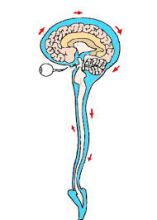

頭蓋仙骨療法とも云います「クラ二オセイクラルセラピー」とは脳脊髄液が脳の硬膜内でゆっくりと一日4~5回位脳脊髄内を髄液が仙骨硬膜内を循環し、脳や脊髄神経を保護したり、必要な栄養を供給したりする作用が有ります 脳の内側で作られ、そこから、脳や脊髄をめぐり一日に何回か入れ替わっています。又脳脊髄液が何らかの原因で増えすぎると、脳圧が高まります、反対に事故等の原因により、脳脊髄液の漏れから髄液量が低下した場合は脳に衝撃が加わりやすくなり、頭痛やふらつき、目まい、体のだるさや、体調不良等の症状が出ます、頭蓋骨の後頭骨・仙骨の歪みの改善で脳脊髄液の流れがスムーズに流れる様になり循環が正常に流れる様になります、本格的な三角ブロックを使用したクラニオセイクラルセラピー「頭蓋骨仙骨療法」が出来る、東洋整骨院に相談して下さい